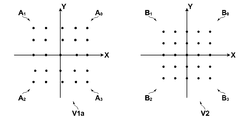

- the first image V1a and the second image V2 deformed according to the angle instead of the distance may be divided.

- a value obtained by replacing the distance d in the expression (3) with the angle ⁇ can be used as the evaluation function.

- the first image and the second image which are deformed according to one spatial parameter called the angle from the reference graphic, are divided, and according to the angle from the reference graphic (reference x-axis).

- Te range theta 0 predetermined angular, theta 1, theta 2, ..., every theta k, if the information specifying the corresponding respective first image and the second image stored in the memory, modified